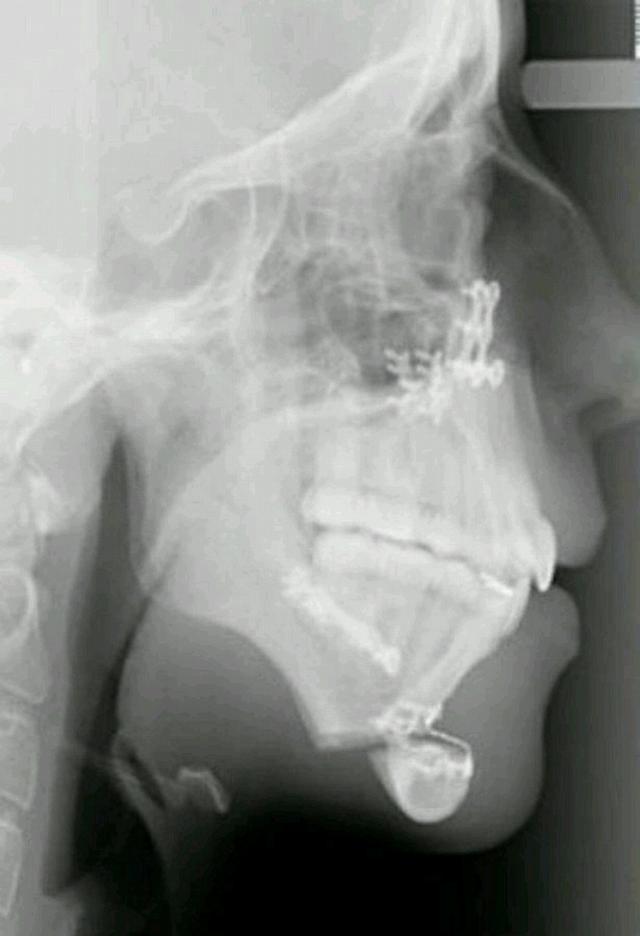

The truth behind her underdeveloped jaw came to light when she was just 14-years old. Because the dental problem was visible. Not only did she need to deal with the bullying but her deformed jaw misaligned her teeth and caused her physical pain. Those years of her life were the worst thing she could imagine…

When the young woman from Ryhl, Wales went to an orthodontist, she was surprised to see that her jaw hadn’t grown since she was 8-years old.

For six years, Ellie went through surgeries to fix her jaw and make her look normal. Because if she didn’t the bullying would never end and she might have to resort to drastic tactics.

Ellie's orthodontist Joy Hickman once discovered the reason her jaw looked different, her consultant maxillofacial surgeon, Emma Woolley, to help this girl’s life.

Her first surgery was done when she was 16. It was a success, she had the pain which was intolerable and she had to be on a liquid diet for a month. Plus, she couldn’t speak and needed to use a notepad for communication – but the struggle was all worth it in the end.